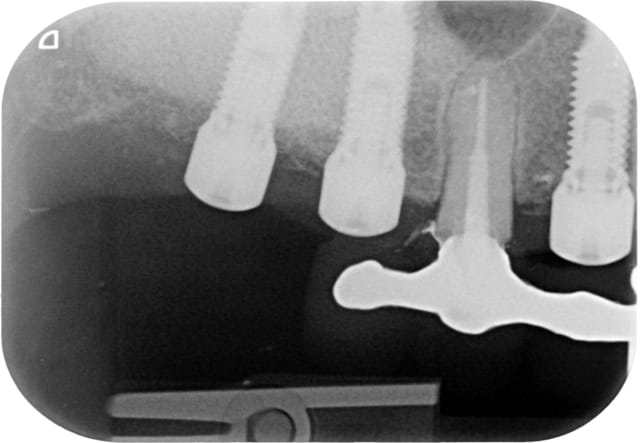

Bon alors revenons a cette 15.

On voit bien sur l'historique radio que la migration apicale a débuté entre janvier et mai 2014. Date à laquelle j'ai dû changer la 14.

J'aime bien les points de contacts assez serrés et là j'ai le souvenir qu'il était très costaud.

Je pense donc que la migration est dû a une compression de la 15 par effet de coin comme la supputer Shadow.

De toute manière maintenant elle ne bougera plus!

A 10 mars 2008 hjqdhq - Eugenol

B 22 mai 2009 fhhmrm - Eugenol

C 04 juin 2009 vjcx5r - Eugenol

D 15 juin 2009 od7vwg - Eugenol

E 25 juin 2009 hht4ji - Eugenol

F 18 novembre 2009 hhywkg - Eugenol